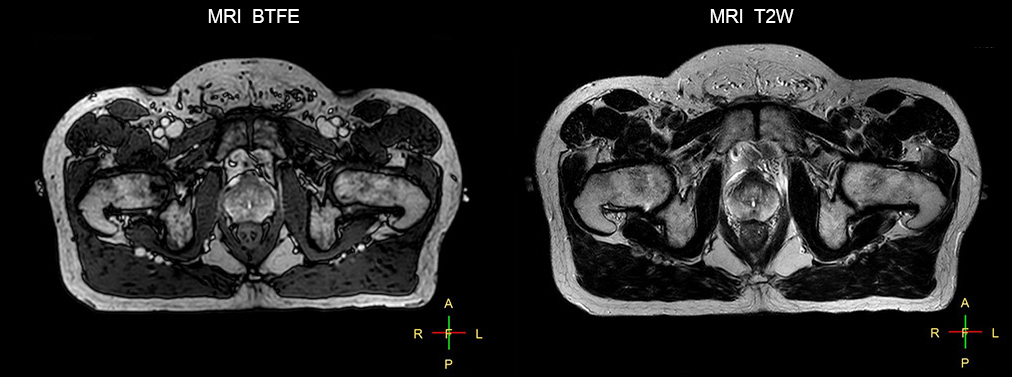

“The biggest problem for CT-based planning, especially in prostate, is you can’t see the cancer very well,” says Dr. Stevens. “On CT it can be quite challenging to see the edge of the prostate especially at the apex. When the edge of the prostate can’t be delineated well on CT, radiation oncologists will increase their margins a little bit so they don’t miss it, but that can also increase toxicity.” “Using MR, the prostate is well delineated. We quickly see the edges of cancerous tumors like in prostate cancer, and as normal structures can be defined, we can optimize the treatment plan to protect these organs and their normal function. This can potentially improve the outcome. And it improves workflow as well. We can contour more quickly, confident that the tumor is going to be in the field.” “The Ingenia 3.0T MR scanner provides high resolution allowing us to make scans fast for the patients. It also gives the potential to include methods like MR spectroscopy and diffusion weighted Imaging, which we’re in the process of doing right now,” Dr. Stevens adds.